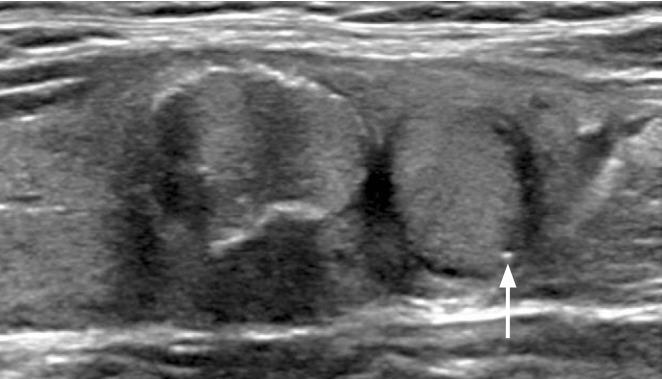

This study was conducted to determine the malignancy risk and diagnostic value of various types of nonshadowing echogenic foci (NEF) in the risk stratification of thyroid nodules.

A total of 1,018 consecutive thyroid nodules (≥1 cm) with final diagnoses were included. The presence of NEF was determined and types of NEF were classified according to the presence of a comet tail artifact (CTA), location, and size through a prospective evaluation. The associations with malignancy, malignancy risk, and diagnostic value of various types of NEF were assessed.

Intrasolid punctate NEF without CTA was the only type of NEF that was an independent predictor of malignancy (P<0.001). The malignancy risk of intrasolid punctate NEF without CTA was substantially higher in solid hypoechoic nodules than in isoechoic or nonsolid nodules (71.3% vs. 9.2%, P<0.001). In solid hypoechoic nodules, slightly increased sensitivity (70.8% vs. 67.9%) for malignancy and a similar malignancy risk (71.4% vs. 71.3%) were observed for intrasolid punctate NEF (with or without CTA) and intrasolid punctate NEF without CTA, respectively. NEF with CTA at the margin of the cystic component was not associated with malignancy or benignity in nonsolid nodules (P>0.05).

Intrasolid punctate NEF without CTA was the only independent predictor of malignancy. However, solid hypoechoic nodules with intrasolid punctate NEF should be classified as high-suspicion nodules regardless of coexisting CTA. Other types of NEF had no added value for detecting malignancy compared to intrasolid punctate NEF without CTA.